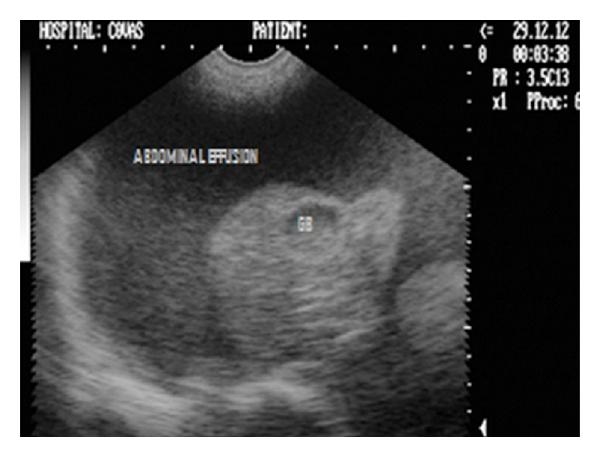

Hepatic disease is often treatable and has a predictable prognosis when a definitive diagnosis is made. The aim of clinicopathological evaluation of hepatobiliary affections is to identify and characterize hepatic damage and dysfunction, identify possible primary causes of secondary liver disease, differentiate causes of icterus, evaluate potential anaesthetic risks, assess prognosis and response to xenobiotics, and monitor response to therapy. This paper describes the different diagnostic methods and imaging techniques employed in diagnosis of hepatobiliary affections in dogs. Besides reviewing the significant clinical manifestations and imaging structural abnormalities in diagnostic approach to different hepatic affections, it also depicts radiographic, ultrasonographic, and wherever applicable, the laparoscopic characterization of different hepatic affections and target lesions encountered in clinical cases presented in the Teaching Veterinary Clinical Complex, COVAS, Palampur in the year 2007-2008.

肝病通常是可治疗的,一旦做出明确诊断,其预后是可预测的。肝胆疾病临床病理评估的目的是识别和描述肝损伤及功能障碍,确定继发性肝病可能的主要病因,鉴别黄疸的病因,评估潜在的麻醉风险,评估预后及对外源化学物质的反应,并监测治疗反应。本文描述了用于诊断犬肝胆疾病的不同诊断方法和成像技术。除了回顾不同肝病诊断方法中的重要临床表现和成像结构异常外,还描述了2007 - 2008年在帕兰普尔兽医临床综合教学中心(COVAS)出现的临床病例中不同肝病及目标病变的放射学、超声学特征,以及在适用情况下的腹腔镜特征。